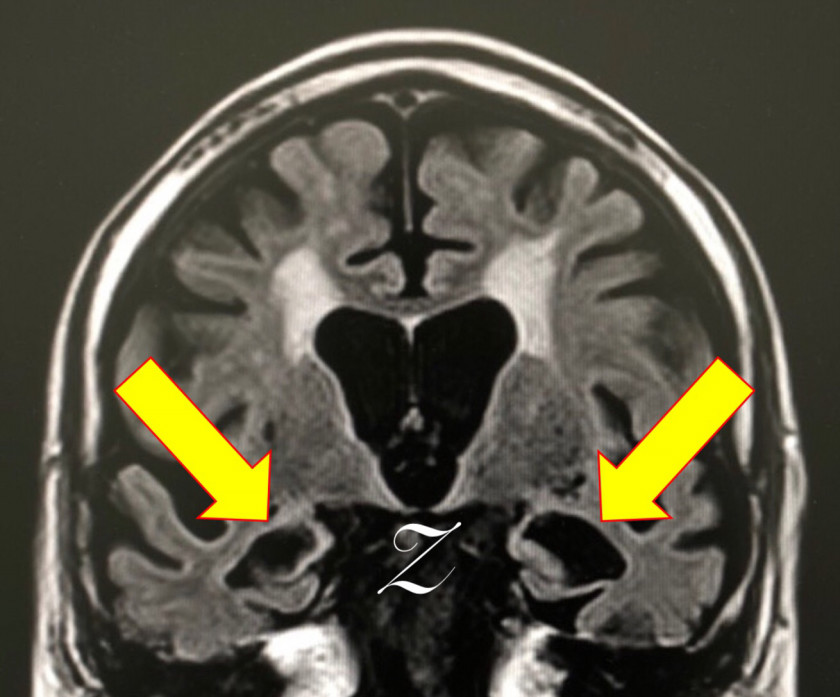

虚血性心疾患の既往もあり。認知機能テストは低得点。MRIも裏付ける内容。他スライスでも明らかな、広汎な白質病変を伴う左右差のある強烈な海馬萎縮。AGDを疑わせるような行動異常は認めず。アルツハイマーにおける海馬萎縮の左右差頻度は拙著に記載した通り、珍しくもなし。年齢的にNFTDとの鑑別は当然だが、過剰リン酸化タウオンリーよりも、アミロイドβ+過剰リン酸化タウのコラボがこの強烈な海馬萎縮の元凶と“妄想”。処方されていたメマリーでノイズを消すことよりも、既往歴と白質病変から考えるに優先すべきことがあるのでは❓

90代前半の症例。風貌は“長身の老紳士”。記憶の問題あり。虚血性心疾患の既往もあり。認知機能テストは低得点。MRIも裏付ける内容。他スライスでも明らかな、広汎な白質病変を伴う左右差のある強烈な海馬萎縮。AGDを疑わせるような行動異常は認めず。アルツハイマーにおける海馬萎縮の左右差頻度は拙著に記載した通り、珍しくもなし。年齢的にNFTDとの鑑別は当然だが、過剰リン酸化タウオンリーよりも、アミロイドβ+過剰リン酸化タウのコラボがこの強烈な海馬萎縮の元凶と“妄想”。処方されていたメマリーでノイズを消すことよりも、既往歴と白質病変から考えるに優先すべきことがあるのでは❓